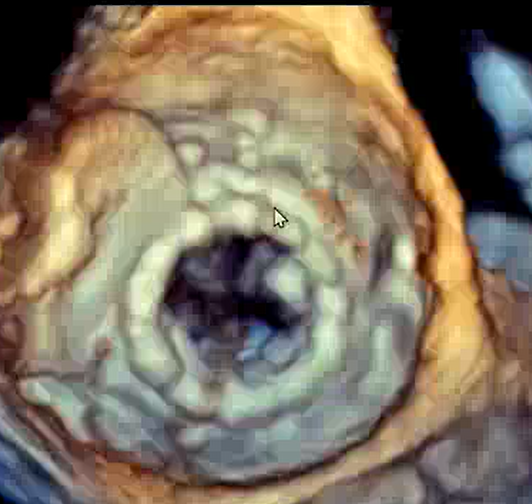

Les valves « antiretour » à l'entrée (mitrale) et à la sortie (aortique) du ventricule gauche sont fondamentales pour assurer un bon fonctionnement de la pompe cardiaque. ...

En Valve-in-Valve mitral : des innovations incessantes

Certaines situations valvulaires étaient jusqu'alors des « impasses thérapeutiques ». C'était notamment le cas de patients contrindiqués à la chirurgie mais porteurs d'une dégénérescence de ...

Tendyne, Intrepid, Cephea…

Quand c'est possible, il est toujours préférable de réparer une valve mitrale mais dans bien des cas, seul le remplacement est possible. ...